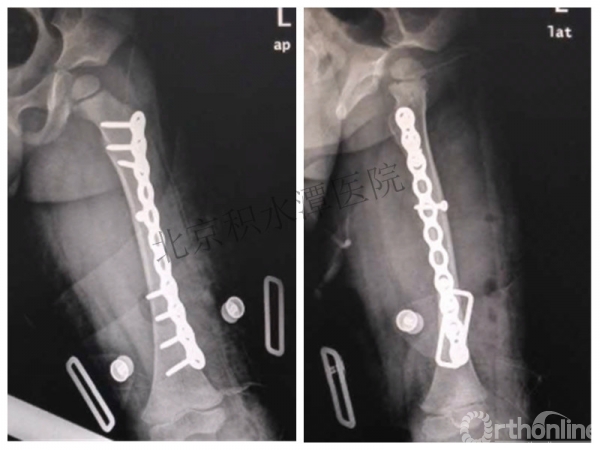

病例分享六

7岁、男孩,桡骨远端骨折

原始损伤片

手法整复后 - 45分钟!

伤后4天复查

伤后30天!

医生的处理方法!——医生终于没有坚持自己的原则!

伤后40天—切开复位内固定!

伤后18个月

如何面对?

心情之压抑无以言表!

手术历时近 5小时!心情之压抑无以言表!因为当时的经治医生是他们的进修生!感觉是他们的失职甚至渎职!

唯一可以肯定—预后不佳!郭教授是党员!是无神论者!但是很诡异的事情:手术中发生—C形臂看不清!拍片条件总是调节不好!手术器械换了三套!内固定钢板总不合适!

术后15月,虽然家长满意了,但是他们医生不满意!